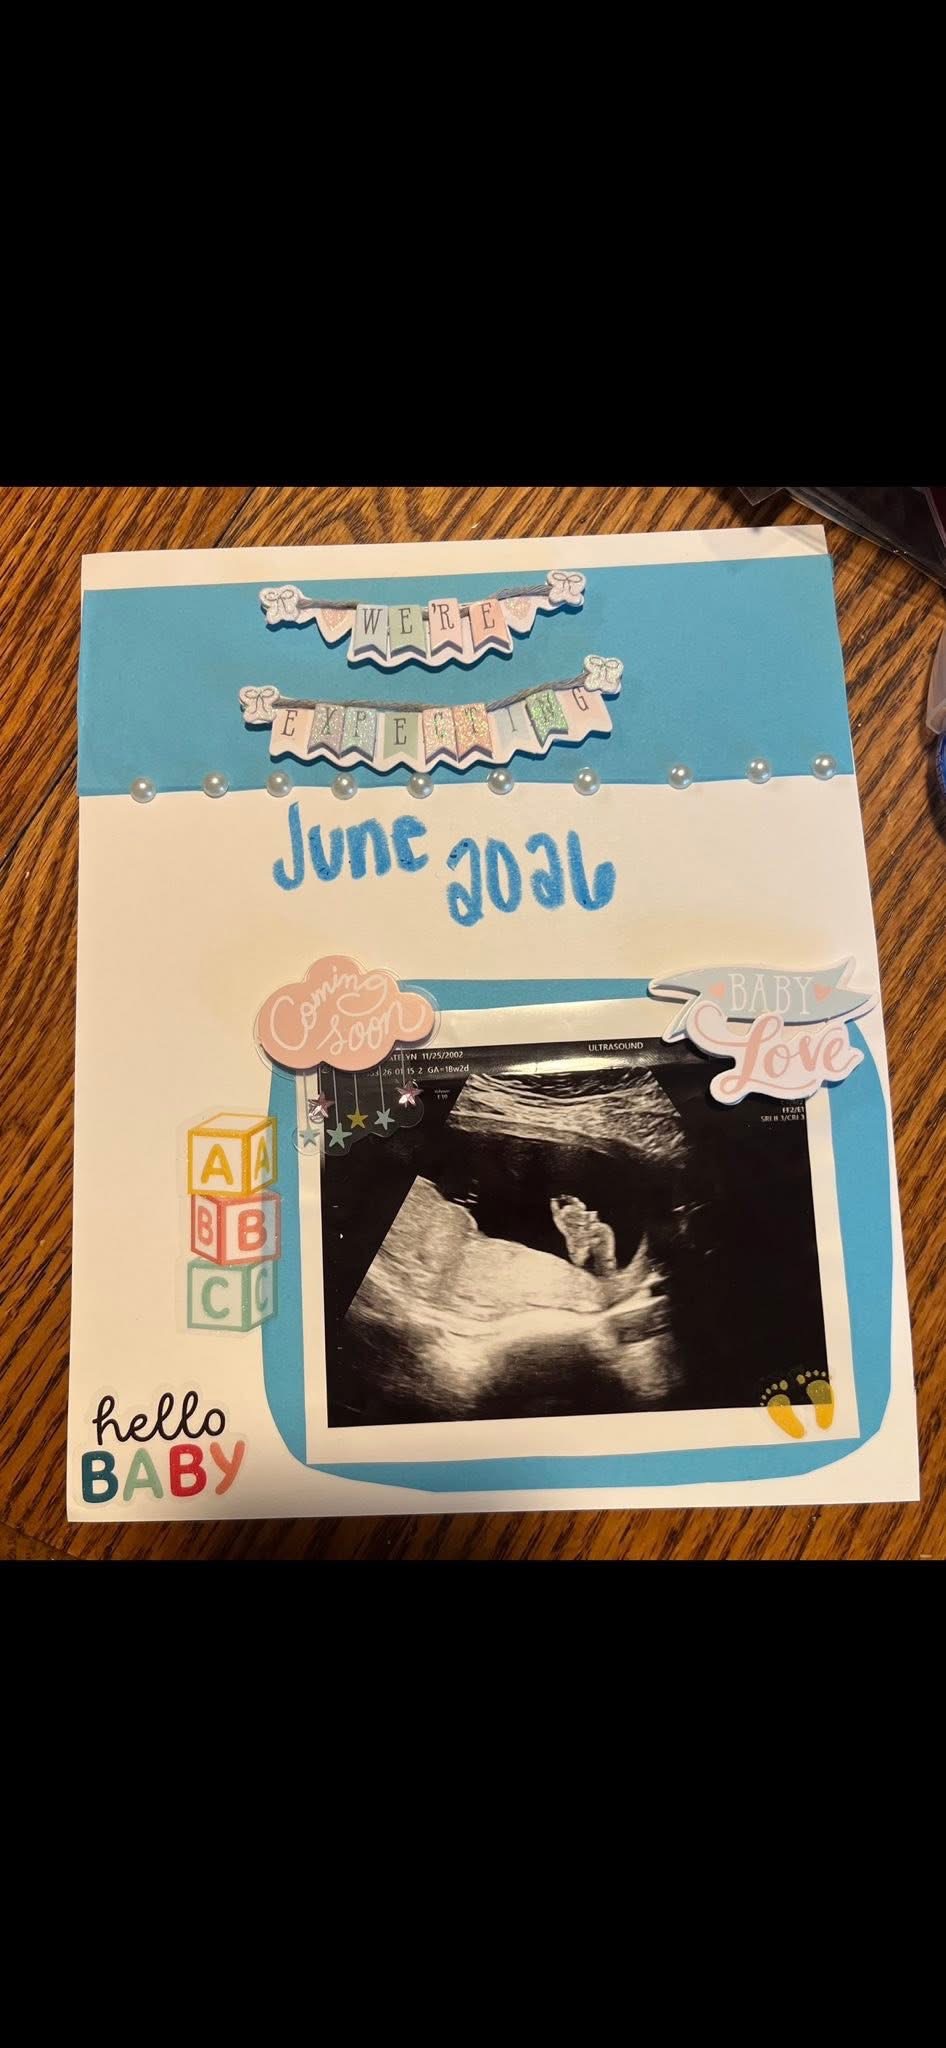

Katie, my sister, went through six months of pregnancy filled with hope and excitement for her baby boy. Tragically, she learned that her baby wasn’t getting enough nutrients through the umbilical cord to support his growth or his lungs. Despite her strength and love, she lost her baby and is now facing the unimaginable pain of saying goodbye before she ever got to meet him.

Katie is a loving and kind person who has always put others first. She is completely heartbroken and feels lost, having prepared everything her baby would need, only to face this devastating loss. No one should have to experience the pain of losing a child, especially after months of anticipation and love.

Katie is a loving and kind person who has always put others first. She is completely heartbroken and feels lost, having prepared everything her baby would need, only to face this devastating loss. No one should have to experience the pain of losing a child, especially after months of anticipation and love.